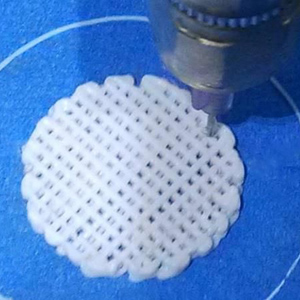

Svrha projekta BIDEAS je razvoj tehnologija i postupaka za proizvodnju biorazgradivih 3D struktura kao materijala za nadogradnju kosti, odnosno kao potpore zubnom implantatu. Koncept će biti potvrđen kroz razvoj inovativnog biorazgradivog 3D nosača za augmentaciju koštanog tkiva u čeljusnoj i parodontalnoj kirurgiji. Inovativnost rješenja očituje se i kroz personalizaciju implantata.